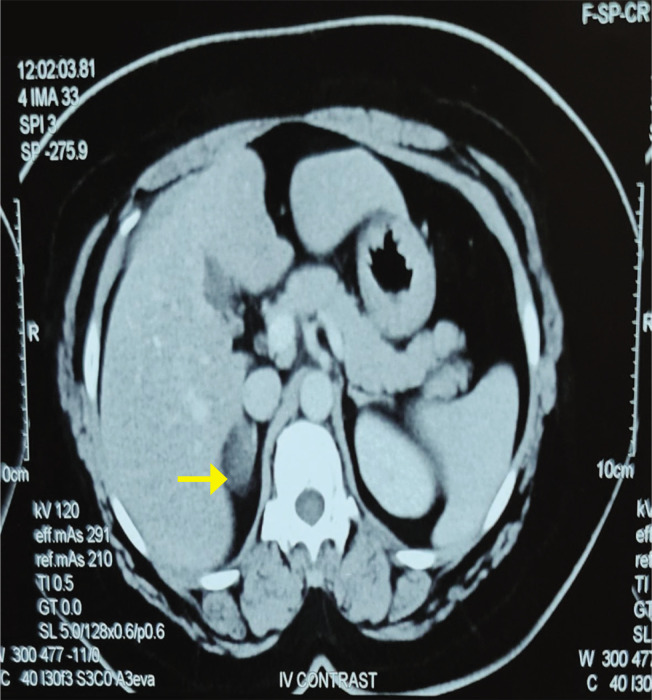

肾上腺髓磷脂瘤(AML)是一种罕见的良性、无症状、无功能的肾上腺皮质肿瘤。AML可同时伴有其他几种内分泌紊乱。在此,我们报告一例36岁女性原发性甲状腺功能减退和代谢综合征,并伴有严重高血压和嗜铬细胞瘤。然而,切除肾上腺的组织病理学检查证实为骨髓脂肪瘤。手术后,她的血浆去甲肾上腺素水平降至正常值,患者血压正常,这表明肿块功能正常。

Adrenal myelolipoma (AML) is a rare, benign, asymptomatic, nonfunctioning tumor of the adrenal cortex detected incidentally. AML can be accompanied by several other endocrine disorders simultaneously. Here, we report a case of a 36-year-old female with primary hypothyroidism and metabolic syndrome accompanied by severe hypertension and pheochromocytoma. However, the histopathological examination of the excised adrenal gland confirmed myelolipoma. Following surgery, her plasma nor-metanephrine levels decreased to normal values and the patient became normotensive, which suggested that the mass was functioning.